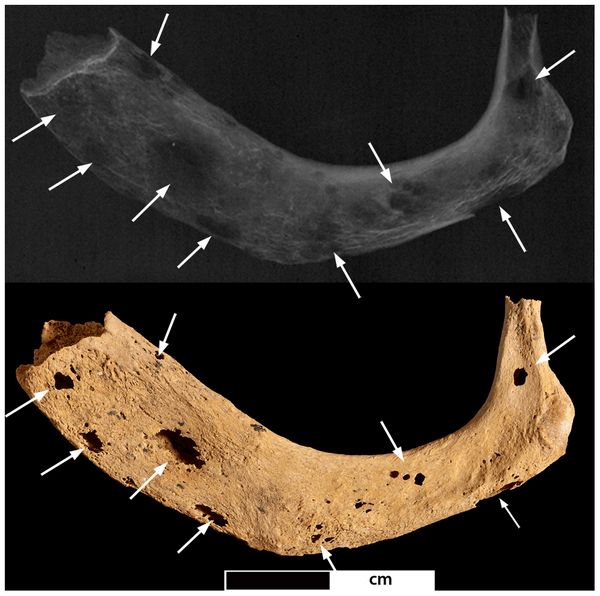

Prima della recente scoperta sudafricana, il più antico tumore maligno osservato in un fossile umano era un cancro presente nella mandibola di un esemplare di Homo ritrovato nel 1932 a Kanam, in Kenya, dal paleontologo britannico Louis Leakey. L’osso risale al Pleistocene e ha un’età di circa 1 milione di anni, ma ci sono ancora dubbi sulla datazione corretta, così come ci sono dubbi sul tipo di tumore presente, identificato dagli studi ogni volta come una neoplasia diversa: da osteosarcoma a linfoma di Burkitt a osteomielite traumatica.

Sono tante le difficoltà che si incontrano quando si cerca di identificare un cancro in un reperto fossile, amplificate anche dal fatto che i frammenti disponibili sono spesso molto piccoli e che si sa poco o nulla sul “paziente”. Solo la tecnologia riesce a trovare risposta a molte delle domande dei “paleoncologi”: nel caso dell’osteosarcoma scoperto in Sud Africa, ad esempio, la diagnosi è stata possibile grazie all’utilizzo di una microtomografia computerizzata a raggi X in grado di generare immagini in due e in tre dimensioni del piccolo campione disponibile. Questa tecnica, unita al confronto con campioni moderni, ha permesso di scartare altre possibili diagnosi e di arrivare al risultato definitivo.